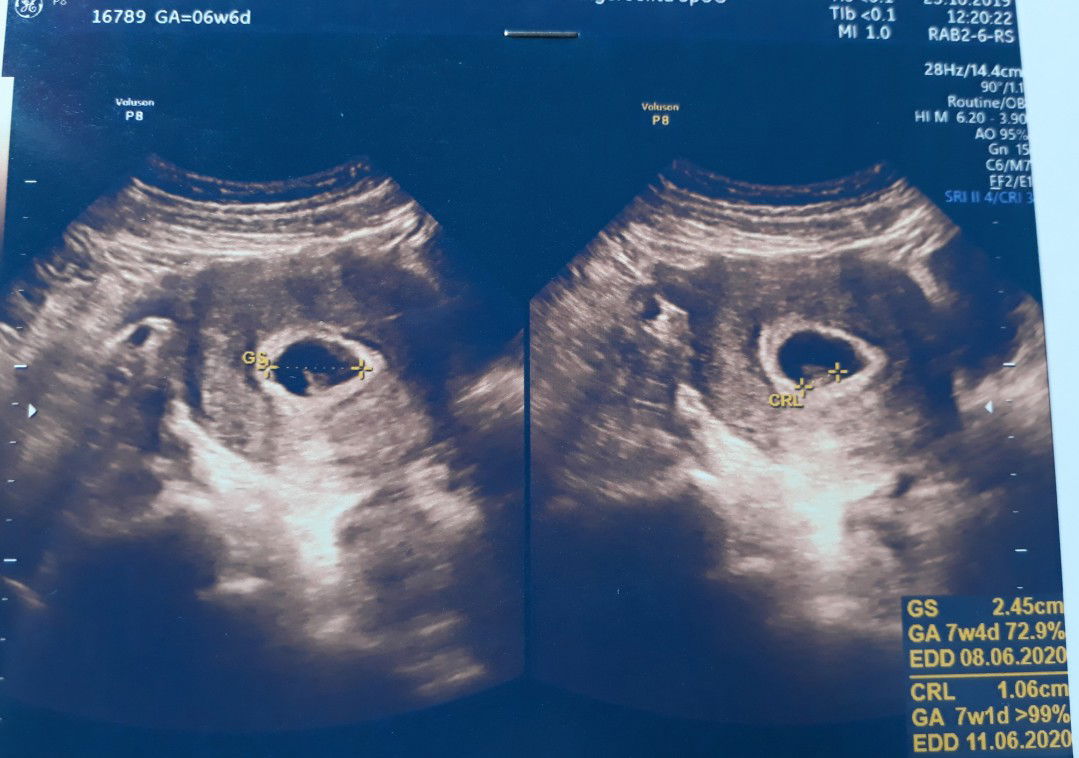

HPHT, GS atau CRL?

Bunda2.. Tadi saya usg ke dokter. Dokternya ngomong cepaaat bgt. Terburu2 gitu. Mungkin karena rame pasiennya. Jadi saya pun lupa apa yg mau saya tanyakan. Makanya saya mau tanya ke bunda2. Mungkin bunda ada yg ngerti. Berdasarkan HPHT = 6w6d. Kalau GS = 7w4d. Dan kalau CRL = 7w1d. Jadi yang benar usia janin saya yg mana ya? Saya jadi bingung sendiri.